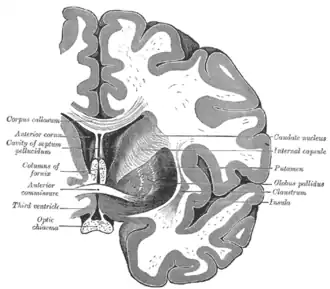

Caudate nucleus

Caudate nucleus (in red) shown within the brain

Caudate nucleus within the skull